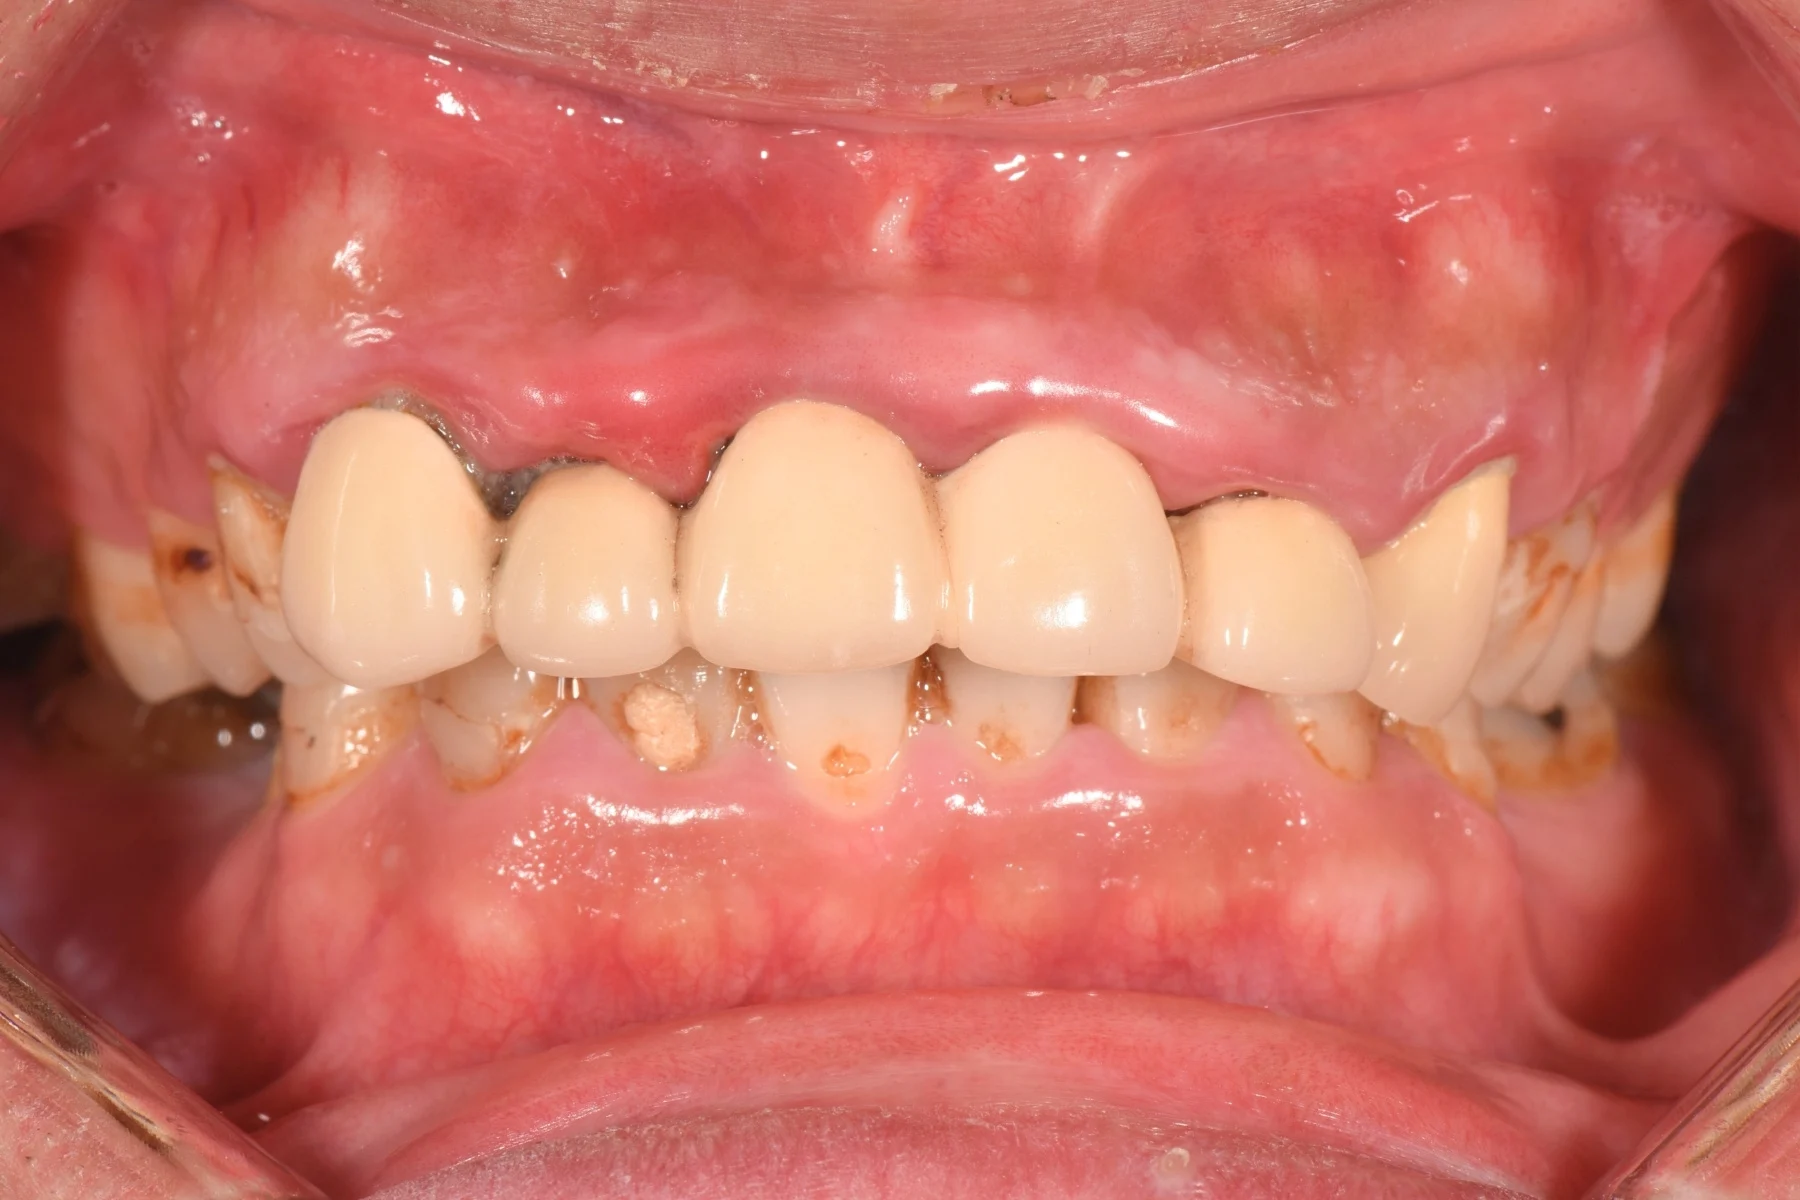

Dentist 陳昕 全口照護醫師 看診項目 前牙美學仿生樹脂補牙/全科牙醫 學經歷 臺北醫學大學牙醫系學士 前天主教新店耕莘醫院醫師 前臺北榮民總醫院醫師 亞洲齒列再生研究學會Advance植牙補綴專科訓練 微光私塾牙周雷射微創治療技術訓練 臺灣牙醫顯微美學治療學會會員醫師 中華審美牙醫學會會員醫師 CASE 案例分享 滲透型樹脂修復 主治醫師 陳昕 治療時間 單次療程 主訴 想處理前牙白白的色斑 前牙美學/仿生美學樹脂 主治醫師 陳昕 治療時間 單次療程 主訴 牙齒整齊,但門牙中間縫隙明顯,影響笑容美觀 前牙美學/陶瓷貼片 主治醫師 陳昕 治療時間 約1個月 主訴 兩顆門牙缺角,想要重建外觀 前牙美學/滲透型樹脂修復 主治醫師 陳昕 治療時間 單次療程 主訴 門牙有長期存在的白斑與表面不平整,影響外觀與自信 前牙美學/仿生美學樹脂 主治醫師 陳昕 治療時間 約兩週 主訴 矯正後的黑三角縫問題 前牙美學/仿生美學樹脂 主治醫師 陳昕 治療時間 約三週 主訴 因牙周病產生的黑三角縫 前牙美學/牙冠增長術、仿生全瓷牙冠 主治醫師 陳昕 治療時間 約6個月 主訴 牙齒排列不整、假牙外觀不自然 前牙美學/仿生美學樹脂 主治醫師 陳昕 治療時間 約兩週 主訴 露齒笑時黑三角縫明顯,覺得不好看 前牙美學/仿生美學樹脂+噴砂美白 主治醫師 陳昕 治療時間 約兩週 主訴 露齒笑時有不好看的黑三角縫,容易有茶垢沉澱,讓縫隙更明顯 牙齒美白/噴砂美白+冷光美白 主治醫師 陳昕 治療時間 單次療程 主訴 前牙泛黃且染色明顯,影響外觀與自信 牙齒美白/噴砂美白 主治醫師 陳昕 治療時間 單次療程 主訴 牙齒表面有喝咖啡、抽菸造成的外部染色,影響外觀與自信 點此載入更多 Column 精選文章 FEATURED 精選案例 【牙科修復案例】陶瓷貼片可以做一顆嗎?單顆門牙缺角修復,陶瓷貼片重建自然笑容 2026-01-16 從「假笑」到「自然笑容」的轉變——認識「牙冠增長術」與「仿生全瓷冠」 2025-10-14 Video 精選影音